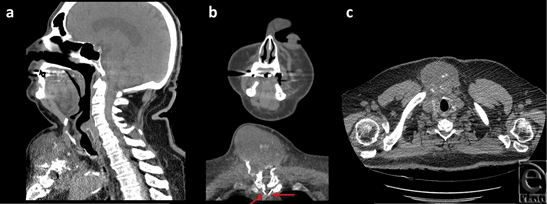

A thorough work-up ensued yielding further details of the mass, as noted on the CT scan (Fig 2) and magnetic resonance imaging (Fig 3), which established this as a 8.4 × 6.2 × 8.6 cm3 complex solid tissue mass within the lower neck arising from the sternal manubrium, with extensive bone destruction. Because of the clinical and radiological appearance, a provisional diagnosis of a sternal granuloma was made.

![]() |

| Figure 4. (a) Gross mass dissected from the anterior side of the sternum measuring 9 × 9 cm2. (b) Surgical field. |